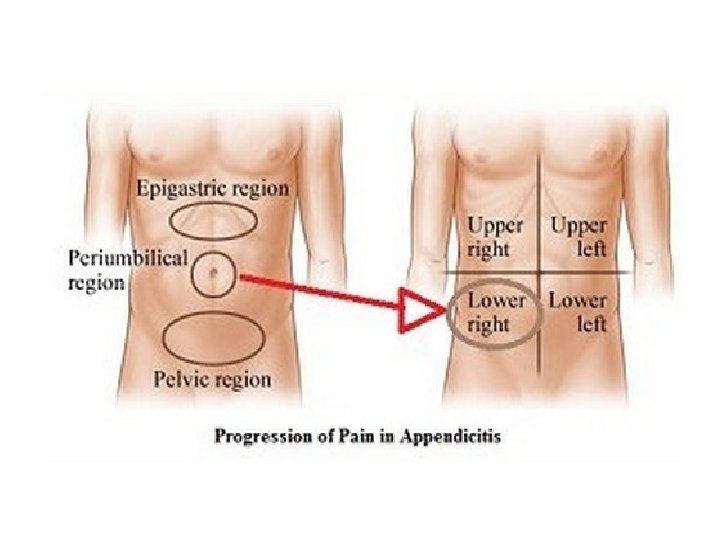

KLINIKA: • DHIMBJA: Fillimisht e moderuar ne forme kolike ne regionin periumbilikal, me pas shnderrohet ne dhimbje te qendrueshme e zhvendosur ne kuadrantin inferior dexter.

NE PALPIM: - Mac Burney (+): 1/3 e poshtme e distances prej umbilikusit ne spina iliake anteriosuperior

- Rebound (+): dhimbja e madhe gjate heqjes se menjehershme te dores palpuese ne kuadrantin inferior dexter. - Defans (+): mbrojtje muskulare ne kuadrantin inferior dexter. - Temperature: subfebrile- e larte, e shoqeruar me frisone +/- te vjella - Leukocitoze - Crregullime te tranzitit: konstipacion, rralle diare.